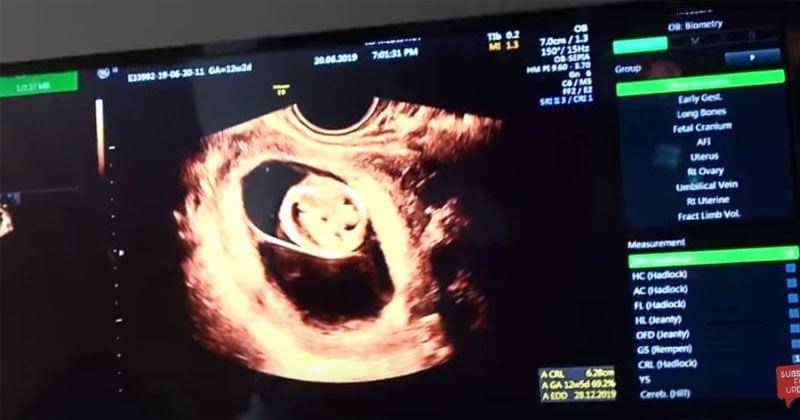

Pada pojok monitor USG yang ada di vlog mereka, terlihat usia janin yang Irish kandung saat ini. Menurut hasil USG, kini Irish mengandung anak kembar dengan usia kandungan 12 minggu 2 hari pada 20 Juni yang lalu.

4. Melakukan USG 4D

Untuk mendapatkan hasil yang maksimal, Ammar dan Irish memilih untuk melakukan USG 4D. Dengan melakukan USG 4D, mereka bisa melihat tubuh janin secara keseluruhan.

Termasuk bisa melihat bagian tubuh janin seperti mulut dan hidung. Dengan menggunakan pemeriksaan USG 4D, maka akan lebih banyak pula detail yang bisa dilihat dari berbagai sudut, sehingga bisa turut membantu mendiagnosis kondisi seperti misalnya bibir sumbing.

Pada pemeriksaan USG 4D, bisa lebih dipastikan juga berapa usia kehamilan dan perkiraan tanggal hari perkiraan lahir atau HPL.

Jumlah cairan ketuban, posisi janin dan aliran darah melalui plasenta juga bisa lebih detail diperhatikan oleh dokter saat menggunakan pemeriksaan USG 4D.